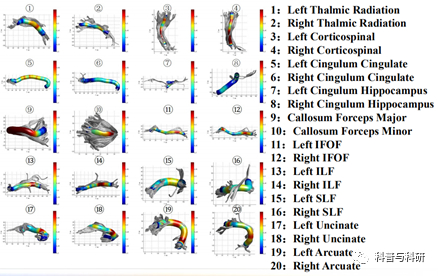

脑白质网络 构建 |

1、基于DTI数据的人脑连接组学方法学介绍 2、弥散磁共振数据的预处理 3、确定性纤维追踪脑网络构建 4、概率性纤维追踪脑网络构建 |

(2)基于ROI-ROI的确定性纤维追踪分析

1 弥散张量成像的配准

2 ROI的空间转换

3 用TrackVis进行纤维追踪

4 纤维束的量化统计与结果展示

(3)基于ROI-ROI的概追性纤维追踪分析

1 弥散张量数据的预处理

2 ROI的提取和空间转换

3弥散方向分布估计BedPostX

4 概率性纤维追踪

5 概率追踪结果的量化统计

(5)纤维自动细分量化技术(AFQ)